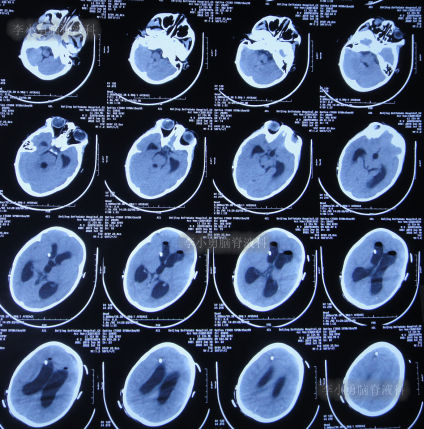

住院治疗7天即2022年5月18日,出现头痛,呕吐,体温再次升高为39.6度,心电图示室性心动过速,室早,考虑“心肌炎”,查头颅核磁(图-1)后并行腰穿见脑脊液呈金黄色,留取脑脊液送常规化验提示诊断为颅内感染,给予抗感染治疗。

图-1:2022年5月18日头颅核磁